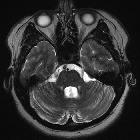

MRI

A stalk-like connection to the clivus is usually seen if high-resolution images are obtained.

Apart from the characteristic location (retroclival, prepontine, and intradural), MRI findings are non-specific, with signal similar to CSF:

- T1: hypointense

- T2: hyperintense

- T1 C+ (Gd): variable, however, most cases have not shown substantial enhancement